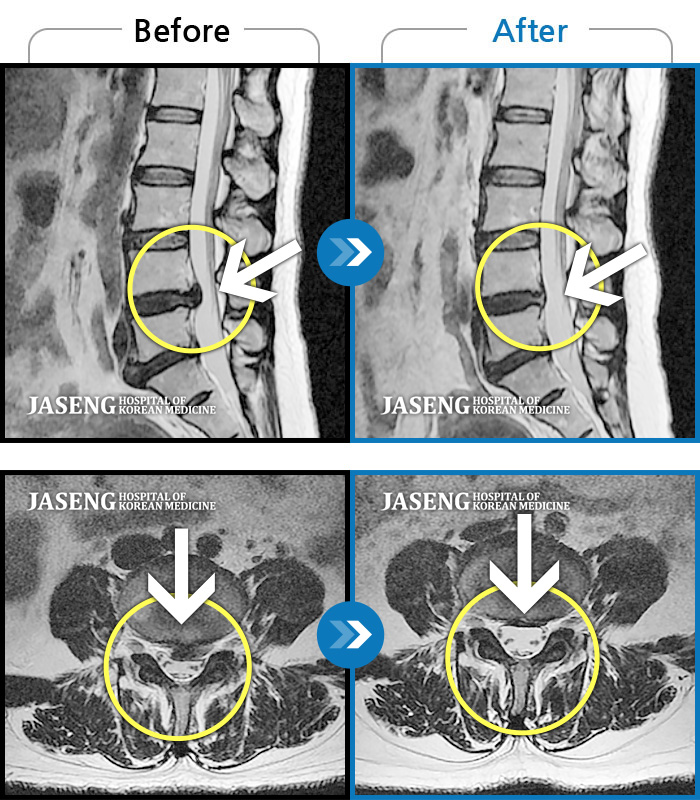

허리디스크

일산 · 김창연 원장

우측허리와 골반쪽의 통증으로 허리를 거의 90도 정도 구부려서 보행

촬영시기

2016.10.23 ~ 2017.05.22

2017.06.02